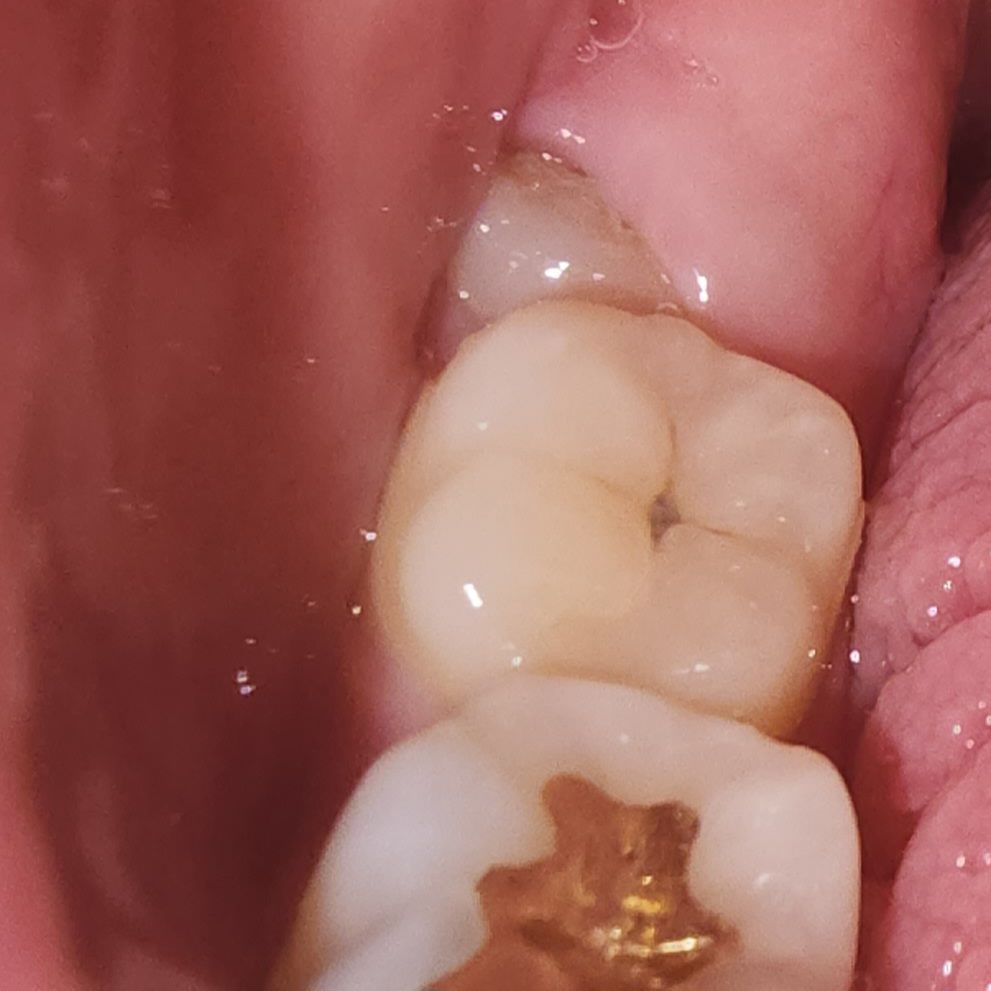

근데 엊그제부터 하루종일 잇몸인지 치아인지 어금니쪽에 물이 닿아도 시리고 바람을 닿게?해도 시리더니 가만히 있어도 아프길래 사진 찍어봤더니

위에 저렇게 작게 뽀족 티어나온게 하나 있고

아래에 잇몸이 부어서 덮어진건지 제일 안쪽이 저렇게 되어있더라고요ㅠㅠ

지금으로서는 진통제를 먹을 수 밖에 없습니다. 위쪽 치아는 연조직 질환이거나 치아 자체의 문제로 인하여 나타났을 가능성이 크고 아래쪽은 사랑니로 인한 통증일 가능성이 큽니다. 현재로서는 치과 방문 후 사랑니를 발치하고 위쪽 치아는 원인을 빠르게 찾아보는 것이 필요합니다.

위쪽사진은 잇몸에 염증이 생겨서 그러신거 같고 아래쪽은 사랑니 때문에 잇몸이 부은거 같습니다. 치과에 가셔서 잇몸치료를 받으시는게 좋을것같습니다.